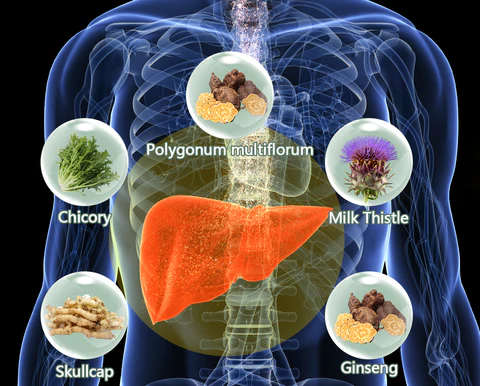

AAFQ™ Polygonum Multiflorum and Ginseng Extract Herbal Spray is specifically formulated to address conditions such as fatty liver, alcoholic hepatitis, liver fibrosis, obesity, insomnia, cirrhosis, hair loss, jaundice, gallbladder disease, and liver dysfunction. Our formula is designed to provide powerful liver support through sublingual absorption, activating liver cell regeneration, repairing the liver, enhancing detoxification capabilities, reducing inflammation, and decreasing visceral fat. By using our spray, you can expect increased energy and vitality within 8 weeks, helping you regain robust liver detoxification function.

AAFQ™ Polygonum Multiflorum and Ginseng Extract Herbal Spray is specifically formulated to address conditions such as fatty liver, alcoholic hepatitis, liver fibrosis, obesity, insomnia, cirrhosis, hair loss, jaundice, gallbladder disease, and liver dysfunction. Our formula is designed to provide powerful liver support through sublingual absorption, activating liver cell regeneration, repairing the liver, enhancing detoxification capabilities, reducing inflammation, and decreasing visceral fat. By using our spray, you can expect increased energy and vitality within 8 weeks, helping you regain robust liver detoxification function.

AAFQ™ Polygonum Multiflorum and Ginseng Extract Herbal Spray” is designed for sublingual absorption, allowing its ingredients to act on the liver through the bloodstream. It stimulates rapid regeneration of liver cells and enhances detoxification effects, providing liver support within one day and promoting liver health restoration. AAFQ™ research team has pioneered an efficient extraction technique that combines active components from various herbs, enabling you to achieve a healthy liver within four weeks.